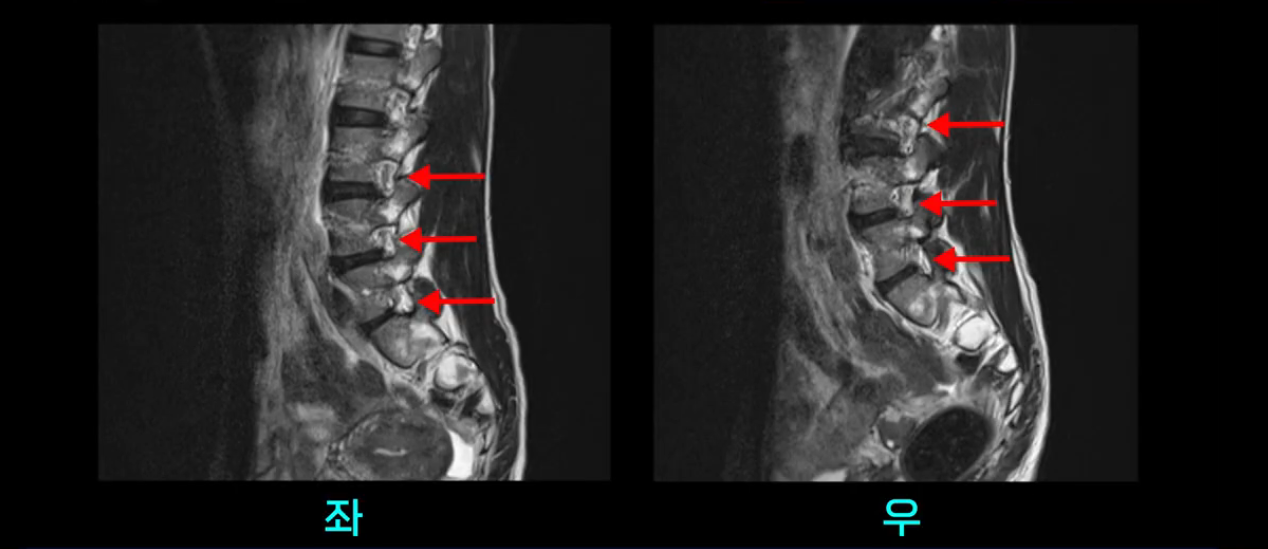

우선 이분의 MRI를 보고 먼저 설명을 드린 후 이런 환자분들의 통증의 원인은 무엇인지, 그리고 치료는 어떻게 해야 하는지 자세히 설명 드리겠습니다.

이분 MRI를 보시면 두 마디의 퇴행성디스크가 있습니다. 그리고 디스크가 조금씩 밀려 나와 있고요. 그런데 디스크 탈출 정도는 두 마디 다 심하지 않습니다. 4번 5번에는 디스크 탈출이 약간 있고,

척추관협착도 약간 진행이 되고 있고요.

5번 1번은 디스크 탈출이 가운데 쪽으로 살짝 있습니다.

또한 양쪽 신경 가지가 빠져나가는 추간공은 매우 넓은 상태입니다.

중요한 것은 이 정도 경미한 탈출과 협착으로는 양쪽 다리가 저리고 아플 수가 없습니다.

그리고 만약에 이 디스크가 급성으로 찢어진 것이라면 아주 심한 디스크성 통증이 있겠죠. 기침이나 재채기를 하면 심하게 아프고 허리를 조금만 구부려도 아주 날카로운 통증들이 생길 겁니다. 그런데 이분은 이런 증상이 전혀 아닙니다. 디스크의 돌출 정도와 협착이 전혀 심하지 않기 때문에 이분이 가지고 계신 양쪽 다리 저림, 특히 이분은 누워있을 때도 양쪽 다리가 저리다고 하는데, 디스크 때문에 그런 증상은 생길 수가 없습니다. 또 이 디스크는 오래된 디스크, 이미 찢어진 섬유륜이 아문 디스크이고, 그러니까 이분은 기침이나 재채기를 못하는 증상이 없는 거죠. 그 다음에 허리를 구부릴 때 뻐근한 증상은 있지만 아주 날카로운 통증은 없습니다.

이처럼 이분의 가벼운 디스크 탈출은 이미 오래 전에 진행되었고 섬유륜 자체는 이미 아문 상태인데도 디스크내장증을 진단받은 환자들 중에는 본인이 섬유륜 파열 환자라고 끝까지 믿는 분들이 많습니다. 다시 말하지만 디스크내장증이라는 진단을 받은 환자들 거의 대부분 섬유륜 파열 증상이 아닙니다. 진단이 잘못되면 어떤 치료를 받아도 좋아질 수 없습니다. 그럼 이분은 다른 여러 병원에서 어떤 얘기들을 들었을까요?

이분 MRI를 보시면 퇴행성디스크가 있고 약간의 협착이 있지만 이 정도의 퇴행성디스크와 협착으로는 신경이 눌려서 양쪽 다리가 저리고 아픈 증상이 나올 수가 없습니다. 그래서 MRI와 이 환자분의 다리 증상이 매치가 안 된다고 하는 의사들이 많은 겁니다.